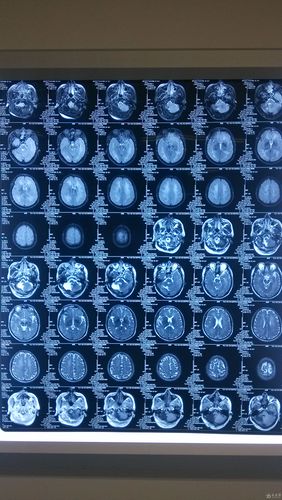

“多发”的含义: “多发”意味着在头颅CT或MRI(磁共振)上发现了两个或以上的梗死灶,这些梗塞灶可能位于大脑的不同区域,说明脑血管的阻塞不是一次性的,而是反复发生的。

什么是“脑白质脱髓鞘”?

核心概念: 我们的脑白质是大脑内部的“电线”,负责连接不同区域的“处理器”(灰质),这些“电线”的外层包裹着一层叫做“髓鞘”的绝缘层,确保神经信号快速、准确地传递。

“脱髓鞘”就是指这层髓鞘发生了损伤、破坏或丢失,导致“电线”裸露,神经信号传递因此变得缓慢、混乱甚至中断。

- 脑白质疏松症: 影像学上的一个描述性术语,常见于慢性高血压、血管病患者,表现为脑室周围白质斑点状或斑片状改变。